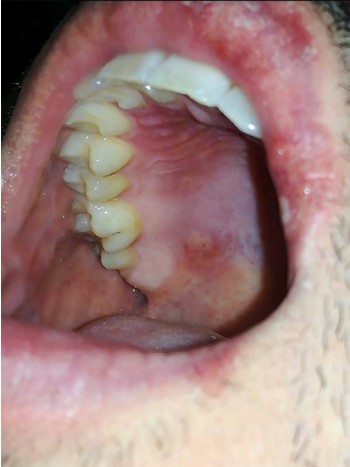

Paciente masculino de 31 años, sin antecedentes médicos de interés ni consumo de medicamentos en la actualidad, que acudió a consulta por haber manifestado, en dos ocasiones luego de 3-4 horas de consumir ginebra con agua tónica “Schweppes®”, una lesión eccematosa en el labio, con formación de úlceras en la cavidad bucal (Figura 1) y una lesión eritematosa fija en la segunda falange de la mano derecha (Figura 2) luego de 24 horas. Las manifestaciones clínicas fueron desapareciendo de forma espontánea; sin embargo, persistió la hiperpigmentación en las zonas durante 2-3 semanas. El paciente refirió haber sufrido, en alguna ocasión, un cuadro con similares características que lo relacionó con el consumo de agua tónica sin ginebra. No refirió la aparición de lesiones con el consumo concomitante de otros alimentos, fármacos ni cofactores adicionales (estrés o consumo de antiinflamatorios).

Se efectuaron estudios alergológicos en el paciente de este caso y en 10 controles sanos. Se llevaron a cabo pruebas cutáneas con aeroalérgenos y alimentos de referencia, que resultaron negativas. Posteriormente se practicaron pruebas cutáneas con cloroquina y agua tónica “Schweppes” al 1/10, también con resultado negativo. Luego de 8 semanas de la reacción adversa se efectuaron pruebas epicutáneas con agua tónica “Schweppes®”, ginebra y quinina al 20% en vaselina, tanto en el área afectada como en las zonas de piel sana, con resultado positivo (++) para ambos productos empleados. Figura 3